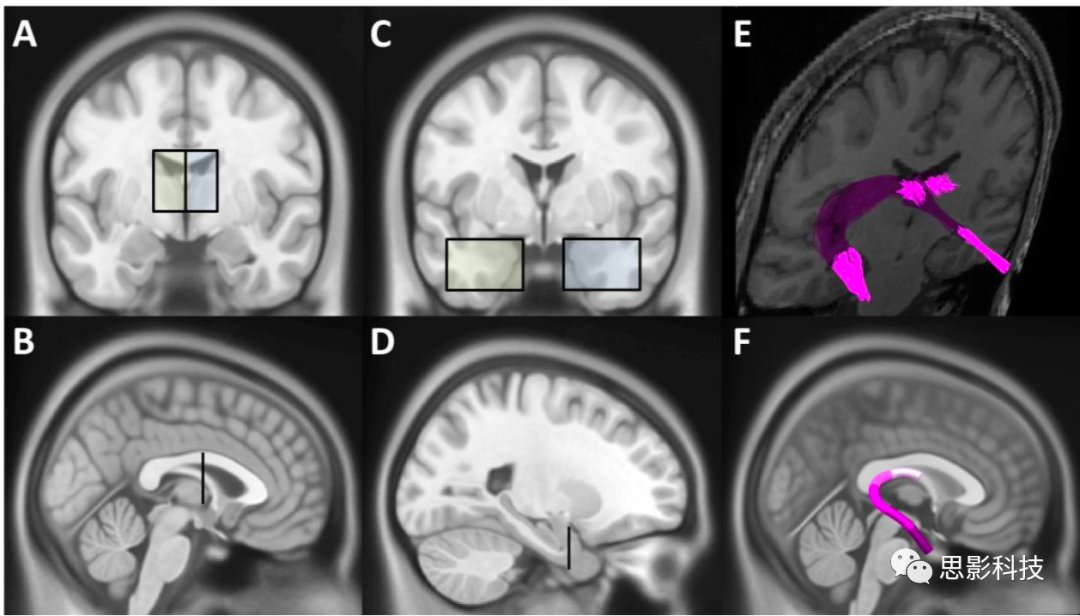

1用于統(tǒng)計(jì)比較的纖維束感興趣區(qū)域的解剖位置。每個纖維束的插圖顯示為單個對象重建的代表性區(qū)域,實(shí)心黑線表示用于AFQ識別的纖維束核心。每個對象的纖維束被映射到模板,并取其平均值以表示每個纖維束的分組。為了進(jìn)行統(tǒng)計(jì)比較,通過平均20個連續(xù)的纖維束部分將每個纖維束劃分為五個感興趣的區(qū)域。感興趣區(qū)編號對應(yīng)于圖2和補(bǔ)充表1中使用的感興趣區(qū)。FF=穹隆海馬傘;PWMB=海馬旁白質(zhì)束;UF=鉤狀束。

補(bǔ)充圖1A-D)冠狀面圖像中的黃色和藍(lán)色陰影矩形和矢狀面圖像中的垂直條顯示了穹隆海馬傘的雙側(cè)感興趣區(qū),包含了穹隆海馬傘從丘腦上方的背側(cè)區(qū)域(AB)到前內(nèi)側(cè)顳葉(CD)的軌跡。(E)代表受試者的雙側(cè)穹窿海馬傘纖維。(F)對于研究中包括的所有受試者,映射到ICBM模板的穹窿海馬傘纖維,其中五個彩色部分代表用于統(tǒng)計(jì)分析的五個ROI。